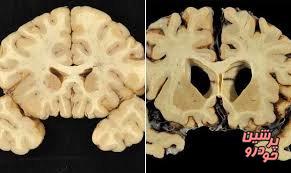

آنسفالوپاتی ترومای مزمن، نوعی بیماری مغزی است که در اثر آسیب‌های ناشی از وارد آمدن ضربه به مغز رخ می‌دهد و می‌توان آن را نوع مجزایی از بیماریهای مغزی در نظر گرفت. پژوهش‌ها نشان می‌دهند که در این بیماری، پروتئین‌های سمی از محل اصابت سر با جسم سخت به سایر نقاط مغز انتقال می‌یابند و جابه‌جایی این ترکیبات سمی بین سلولهای مغز، به التهاب مزمن مغز منجر می‌شود.

مغز

در این پژوهش، 86 ورزشکار سابق که نشانه‌هایی از آنسفالوپاتی ترومای مزمن در آنها وجود داشت، مورد بررسی قرار گرفتند و پژوهشگران، مغز ورزشکاران را برای مشاهده تغییر ژنتیکی در TMEM106B آزمایش کردند.